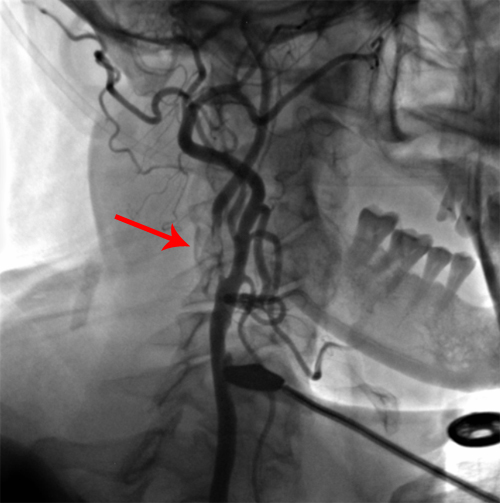

DSA示:双侧颈内动脉中度狭窄。

右侧颈内动脉中度狭窄